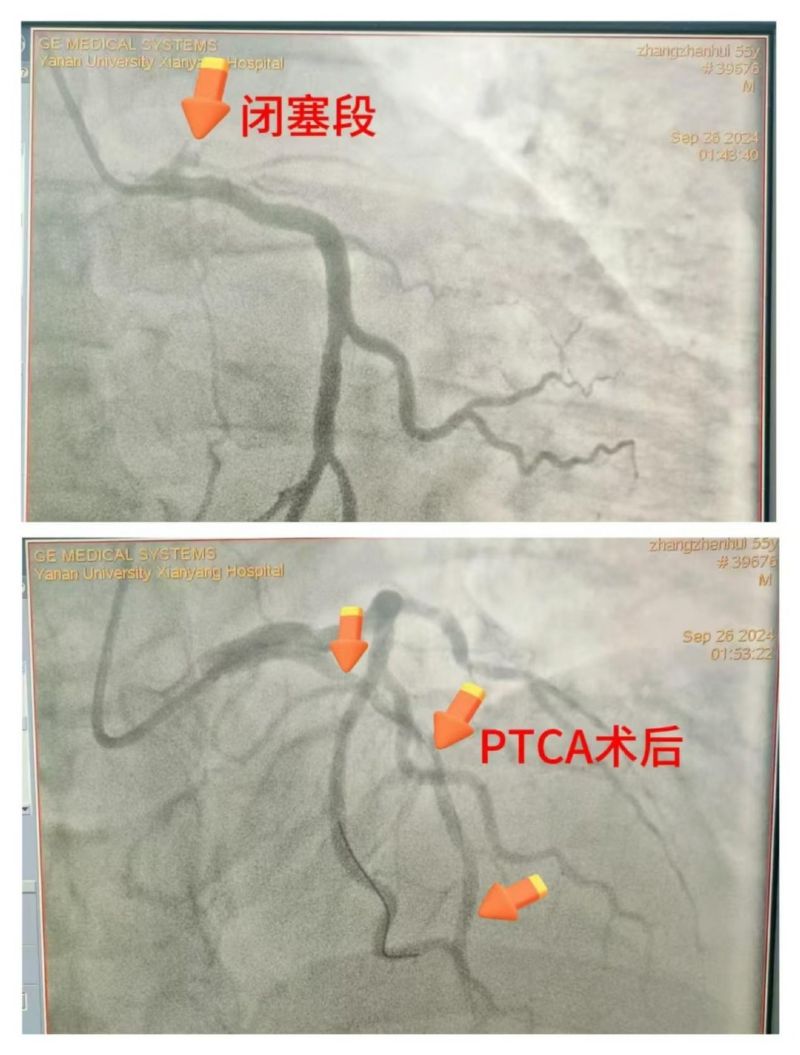

患者仍反復(fù)室顫,考慮與急性心肌梗死、急性胰腺炎導(dǎo)致的電風(fēng)暴相關(guān),唯一的希望是開(kāi)通罪犯血管,但手術(shù)風(fēng)險(xiǎn)極高。李新國(guó)科主任與患者家屬充分溝通病情,家屬理解并配合一切治療方案。立即開(kāi)通胸痛綠色通道,啟動(dòng)導(dǎo)管室行急診冠脈造影,術(shù)中證實(shí)為左前降支近段100%閉塞,緊急行PTCA開(kāi)通罪犯血管,患者心律逐漸穩(wěn)定,血壓回升,意識(shí)好轉(zhuǎn),刺激有反應(yīng),返回CCU繼續(xù)治療。